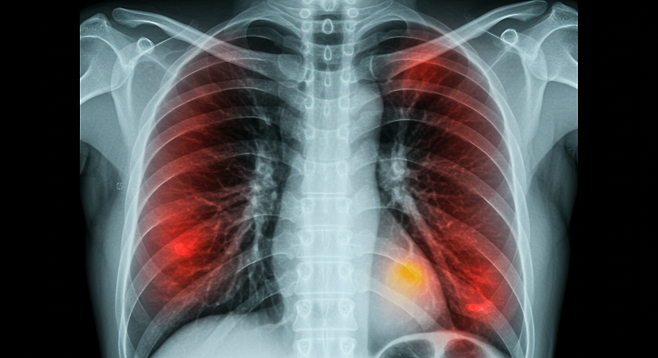

폐암은 국내에서 두 번째로 많이 발생하는 암으로, 조기 발견이 치료 성공률을 높이는 핵심 요소로 꼽히고 있다. 특히 아침에 나타나는 특정 증상들은 폐암의 초기 신호일 수 있어 주목해야 한다.

조기 발견의 중요성

폐암은 초기에는 감기와 비슷한 증상을 보여 진단이 어렵다. 그러나 아침마다 반복되는 기침, 얼굴 부종, 호흡곤란, 피로감 등이 나타난다면 이를 간과하지 말고 전문 검사를 통해 원인을 확인하는 것이 중요하다. 조기 발견만이 생명을 지키는 열쇠다.